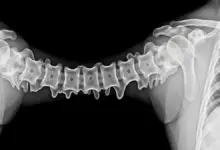

Causas Comuns da Dor na Coluna Lombar

Quando se trata de dor na coluna lombar, o que pode ser? Confira algumas das causas mais comuns:

- Distensões musculares e ligamentares: Essas lesões costumam ocorrer quando a musculatura ou os ligamentos da região lombar são estirados ou torcidos, causando dor e desconforto.

- Hérnia de disco: A hérnia de disco ocorre quando um dos discos intervertebrais da coluna vertebral se desloca e comprime as raízes nervosas, causando dor na região lombar e, às vezes, na perna.

- Estenose espinhal: Esse problema é caracterizado pelo estreitamento do canal espinhal, o que pode comprimir as raízes nervosas e causar dor na região lombar.

- Espondilolistese: A espondilolistese ocorre quando uma vértebra se desloca em relação à vértebra abaixo, causando dor na coluna lombar e instabilidade na região.

- Osteoartrite: A osteoartrite é uma doença degenerativa que afeta as articulações da coluna vertebral, podendo causar dor e rigidez na região lombar.